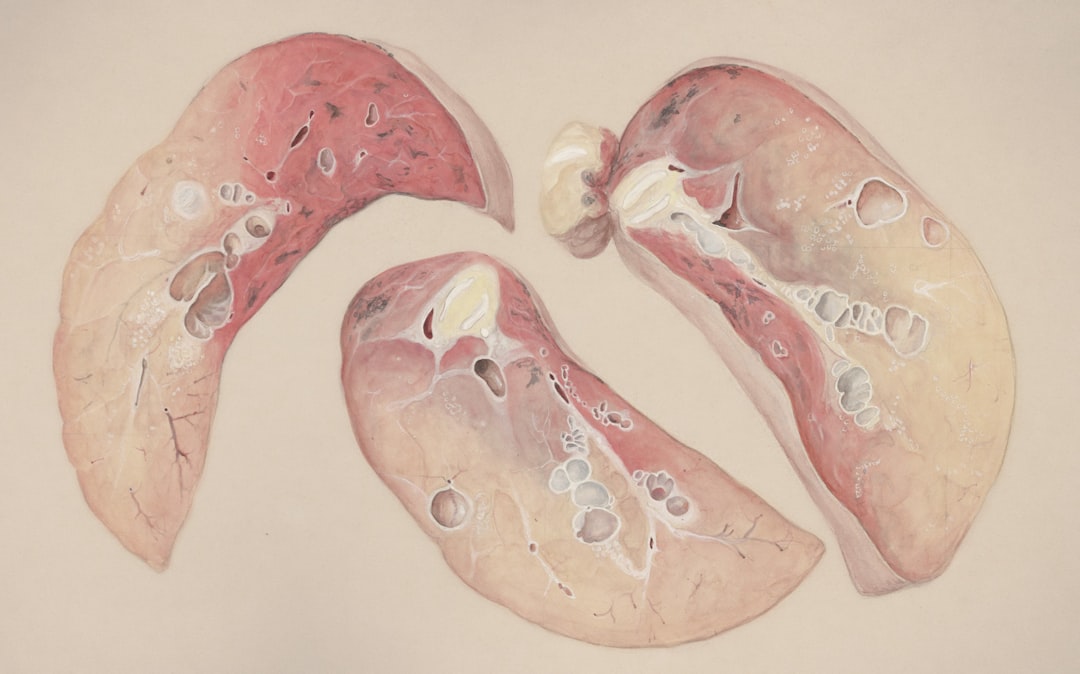

잠복결핵 치료 방법

잠복결핵이 양성으로 판명된 경우, 즉시 치료를 시작해야 합니다. 일반적으로 사용되는 약물은 아이소니아지드 혹은 리팜핀입니다. 치료 기간은 보통 6개월에서 9개월 정도 소요되며, 이 기간 동안 꾸준히 약물을 복용하는 것이 매우 중요합니다. 치료받는 과정에서 잠복결핵 치료 후기 등을 참고하여 스스로의 마음가짐을 다잡는 것도 좋은 방법입니다.

치료 중 부작용으로는 간염, 위장 문제 등이 있을 수 있습니다. 그러나 대부분의 환자는 치료 초기 몇 주 이후에는 큰 불편함을 느끼지 않으며, 치료를 받는 것이 건강 유지에 큰 도움이 됩니다. 아래 표를 통해 각각의 약물에 대한 특징을 한눈에 살펴볼 수 있습니다.